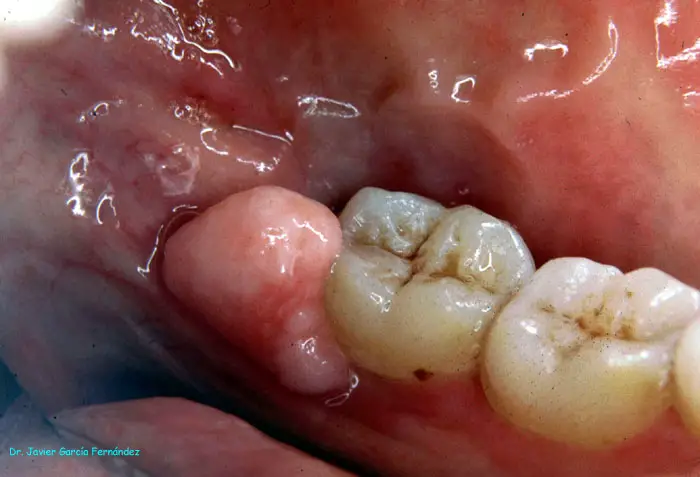

Atlas of Surgical Techniques in Periodontics. Chapter I. Diagnostic of Peridontal Diseases. Classification. Atlas de Técnicas Quirúrgicas en Periodoncia. Cap. I. Classification. Atlas de Técnicas Quirúrgicas en Periodoncia